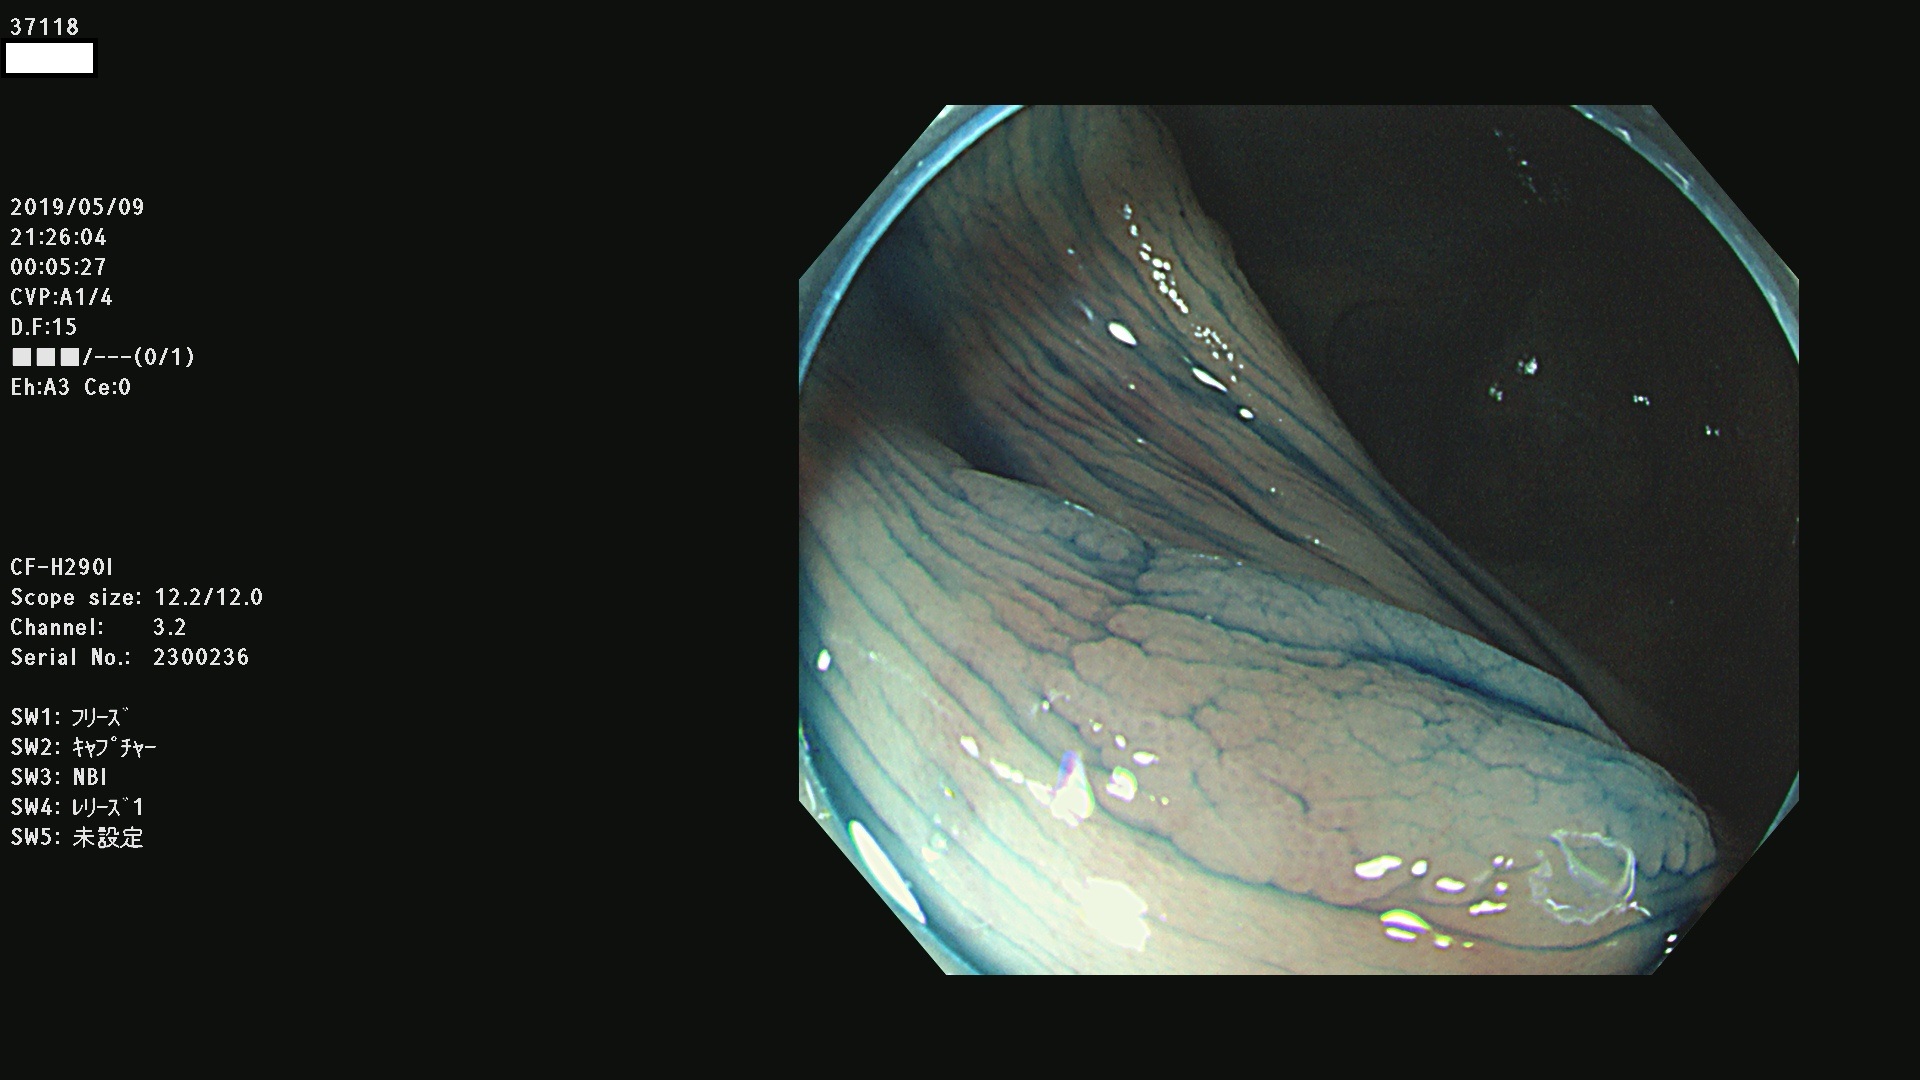

37100 37101 37102 37104 37106 37108 37110 37111 37112 37113 37115 37118(SSAPのみ) 37120 37122 37123 37124 37127(SSAPのみ) 37128(SSAPのみ) 37131 37132 37133 37134 37135 37139 37141 37142 37143 37144(SSAPのみ) 37145 37147(SSAPのみ) 37148 37149 37150 37153 37154 37157 37159 37161 37162 37163 37164 37165 37166 37167 37168 37169 37170 37171 37172 37173 37175(SSAPのみ) 37176 37177 37178 37180(SSAPのみ) 37181 37184 37185 37186 37187 37188 37189 37190 37192 37194 37197 37198

発見困難で危険性の高い平坦型病変(上記100名より抽出)